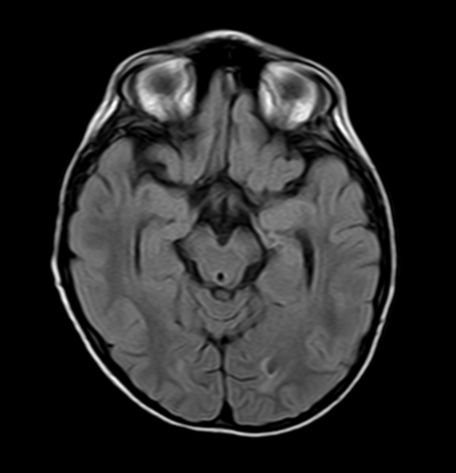

• RM craneal y medular: discreto aumento de señal en secuencia FLAIR y T2 en ambos hipocampos, algo más evidente en el izquierdo.